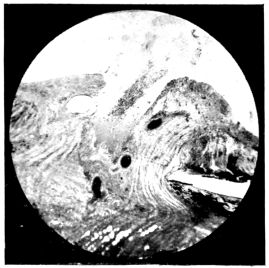

PLATE V.

28.

INJURIES TO UVEAL TRACT

curly bracket span

29.

FOREIGN BODY (TIP OF COPPER PROBE) IMBEDDED IN THE EYE

30.

TRAUMATIC DETACHMENT OF RETINA AND CHOROID

31.

WHOLE-SECTION OF FIG. 19

32.

PART OF THE ABOVE MAGNIFIED TO SHOW LENS IMBEDDED IN INFLAMMATORY EXUDATE

33.

PHAGOCYTOSIS